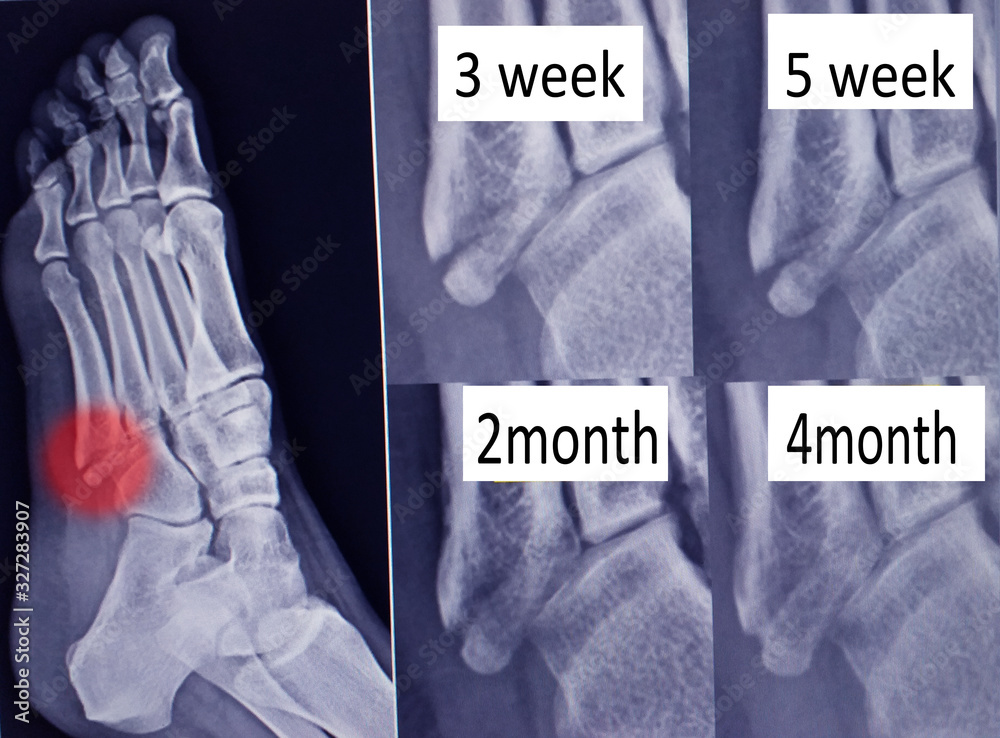

Xray of the Foot. Fracture of the 5th Metatarsal Bone. Marker Stock Metatarsal Fracture X Ray Views Every metatarsal bone consists out of three parts: Radiography is the first and often the only investigation required for the diagnosis of fractures. Displacement is usually minimal unless more than one metatarsal is fractured. Radiographs may be used to diagnose all acute fractures,. Caput ossis metatarsi, corpus ossis metarisi and the basis. Fractures of the 5th metatarsal base are a.. Metatarsal Fracture X Ray Views.

Foto de X ray foot bone fracture ( base of metatarsal fracture ) from Metatarsal Fracture X Ray Views Most metatarsal shaft fractures are oblique or transverse (figure 1a). The foot consists out of 5 metatarsal bones per foot. Metatarsal fractures are among the most common injuries of the foot that may occur due to trauma or repetitive microstress. Caput ossis metatarsi, corpus ossis metarisi and the basis. Radiography is the first and often the only investigation required for. Metatarsal Fracture X Ray Views.